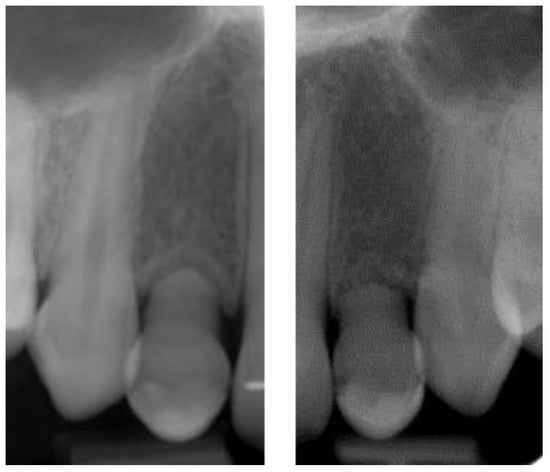

2.4.1. Radiographic Measurements

3.2. Marginal Bone Level Outcomes

| Mesial Marginal Bone Level (2D) [mm] after Immediate Placement | ||||||||

|---|---|---|---|---|---|---|---|---|

| Patient | 1 | 2 | 3 | 4 | 5 | Median | IQR | |

| Implant position | 45 | 35 | 45 | 45 | 13 | 23 | NA | NA |

| Post-OP mesial | 1.8 | 0.0 | 0.1 | 3.0 | 0.4 | 0.4 | 0.4 | 0.18–1.45 |

| 1 year mesial | 0.6 | 0.0 | 0.1 | 1.5 | 0.1 | 0.1 | 0.1 | 0.1–0.48 |

| Post-OP distal | 1.2 | 0.0 | 0.1 | 3.0 | 0.4 | 0.4 | 0.4 | 0.18–1.0 |

| 1 year distal | 0.6 | 0.0 | 0.1 | 1.5 | 0.2 | 0.0 | 0.2 | 0.03–0.5 |

| Marginal Bone Level (2D) [mm] after Delayed Placement | ||||||||

| Implant position | 35 | 45 | 35 | 35 | 35 | 45 | NA | NA |

| Post-OP mesial | 2.0 | 1.0 | 0.2 | 0.6 | 0.2 | 0.2 | 0.4 | 0.2–0.9 |

| 1 year mesial | 1.6 | 0.5 | 0.0 | 0.3 | 0.1 | 0.1 | 0.3 | 0.1–0.45 |

| Post-OP distal | 0.0 | 0.5 | 0.0 | 0.6 | 0.1 | 0.1 | 0.1 | 0.03–0.4 |

| 1 year distal | 0.0 | 0.2 | 0.0 | 0.3 | 0.1 | 0.1 | 0.1 | 0.03–0.18 |